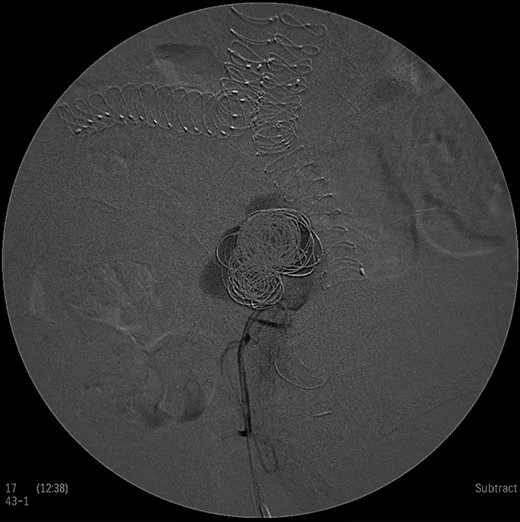

Under general anesthesia the patient was placed in prone position and a 15 cm transverse incision, slightly curvy was performed in the middle part of the right gluteal region between the posterior superior iliac spine and ischiac tuberosity. The gluteus maximus muscle was split and the inferior gluteal artery was identified as it entered the gluteal region through the greater schiatic foramen near the schiatic nerve below the piriformis muscle. The inferior gluteal artery was punctured using Seldinger technique and a 4Fr was introduced into the artery (Fig. 2). An angiography was made revealing the aneurysm of the right IIA and two feeding arteries, inferior gluteal artery and probably a branch of superior gluteal artery, filling the sac (Fig. 3). A 0.014 inch Pilot guide wire (Boston Scientific Corporation, USA) was inserted into the aneurysm and a microcatheter 3 Fr RENEGADE STC (Boston Scientific Corporation, USA) was advanced over the wire. After removing the wire, embolization microcoils (Interlock, Boston Scientific, USA) (two coils 22–600 mm, two coils 20–500 mm, three coils 18–500 mm) were introduced into the aneurysm sac (Fig. 4). A 5 Fr sheath was subsequently placed, a 5Fr RIM catheter (Cordis, USA) was advanced to the aneurysm sac through a 0.035 inch Terumo guide wire (Glidewire, Terumo Corporation, Japan) and selective catheterization of the second feeding artery was performed (Fig. 5). Embolization coils (Interlock, Boston Scientific, USA) were inserted into the two feeding arteries (two coils 15–400 mm) (Fig. 6). Completion angiogram depicted absence of blood flow into the aneurysm and the runoff vessels (Fig. 7). The patient had an uneventful recovery period without buttock claudication, ischemic complications and discharged in good condition. A follow-up CT aortography after 6 months depicted complete thrombosis of the aneurysm (Fig. 8).

Intraoperative angiogram showing the presence of the aneurysm and two collateral vessels, embolization with coils of the sac and two feeding arteries. Completion angiogram depicted absence of blood flow in the IIA aneurysm and the runoff arteries.